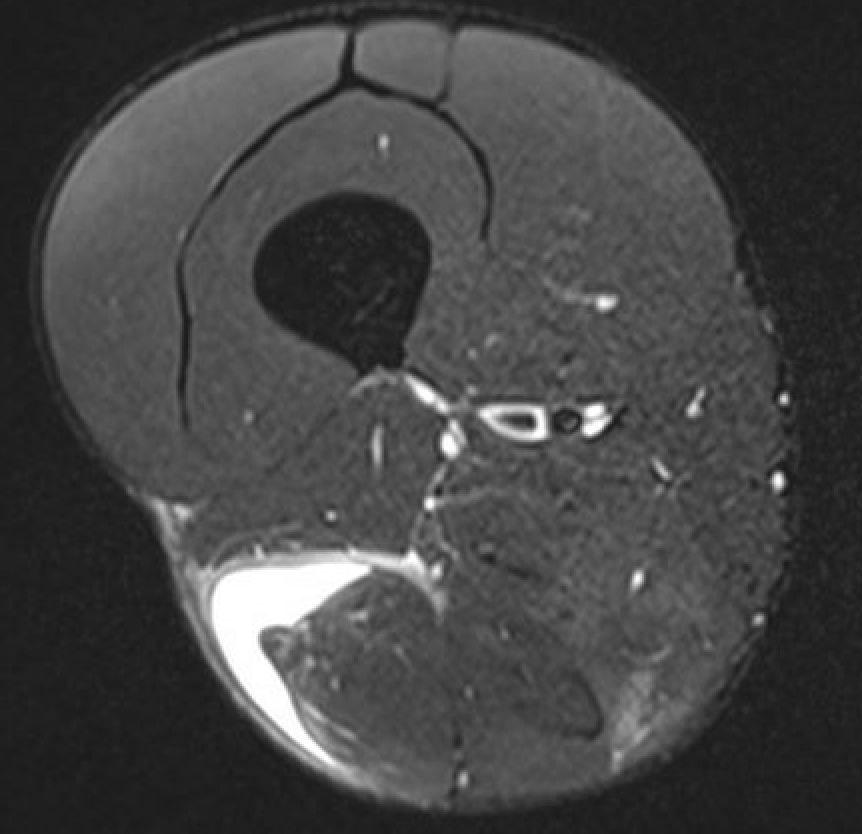

Grade 4 distal biceps femoris T Junction musculotendinous tear